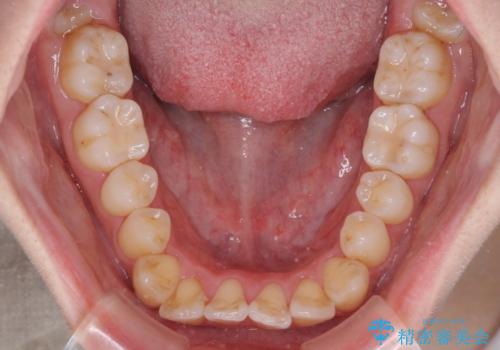

【モニター】前歯の前突感とクロスバイトをインビザラインで改善

- 前歯の突出感とクロスバイトが気になり、インビザラインによる矯正治療を希望して来院された患者様です。

上顎側切歯(上の真ん中から2番目の歯)が舌側転位している場合、インビザラインでは仕上げきれないことが多く、更には無理して動かそうとすると歯髄壊死を起こすリスクが高いと言われています。

インビザラインで歯列を移動する前に、上顎前歯をワイヤー矯正で整え、その後上下歯列をインビザラインにて矯正治療を行うこととしました。

舌側転位している側切歯特有の、切縁の位置が不揃いであったり、根元が内側に引っ込んだ状態であったりという、インビザライン独特の仕上がりになることなく、きれいに整った歯列とすることができました。